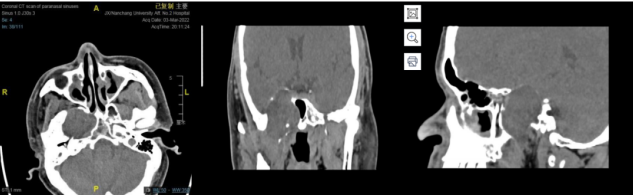

右侧鞍旁见类圆形占位,中央稍低密度,周围环形稍高密度,可见残留骨质密度影,大小约 32☓46 mm,邻近骨质吸收变薄,建议 MRI 平扫+增强扫描。

中颅窝右侧鞍旁可见无强化稍低密度影,边缘可见少许钙化影,边界清晰,邻近骨质受压变薄,邻近颈内动脉受压内移。